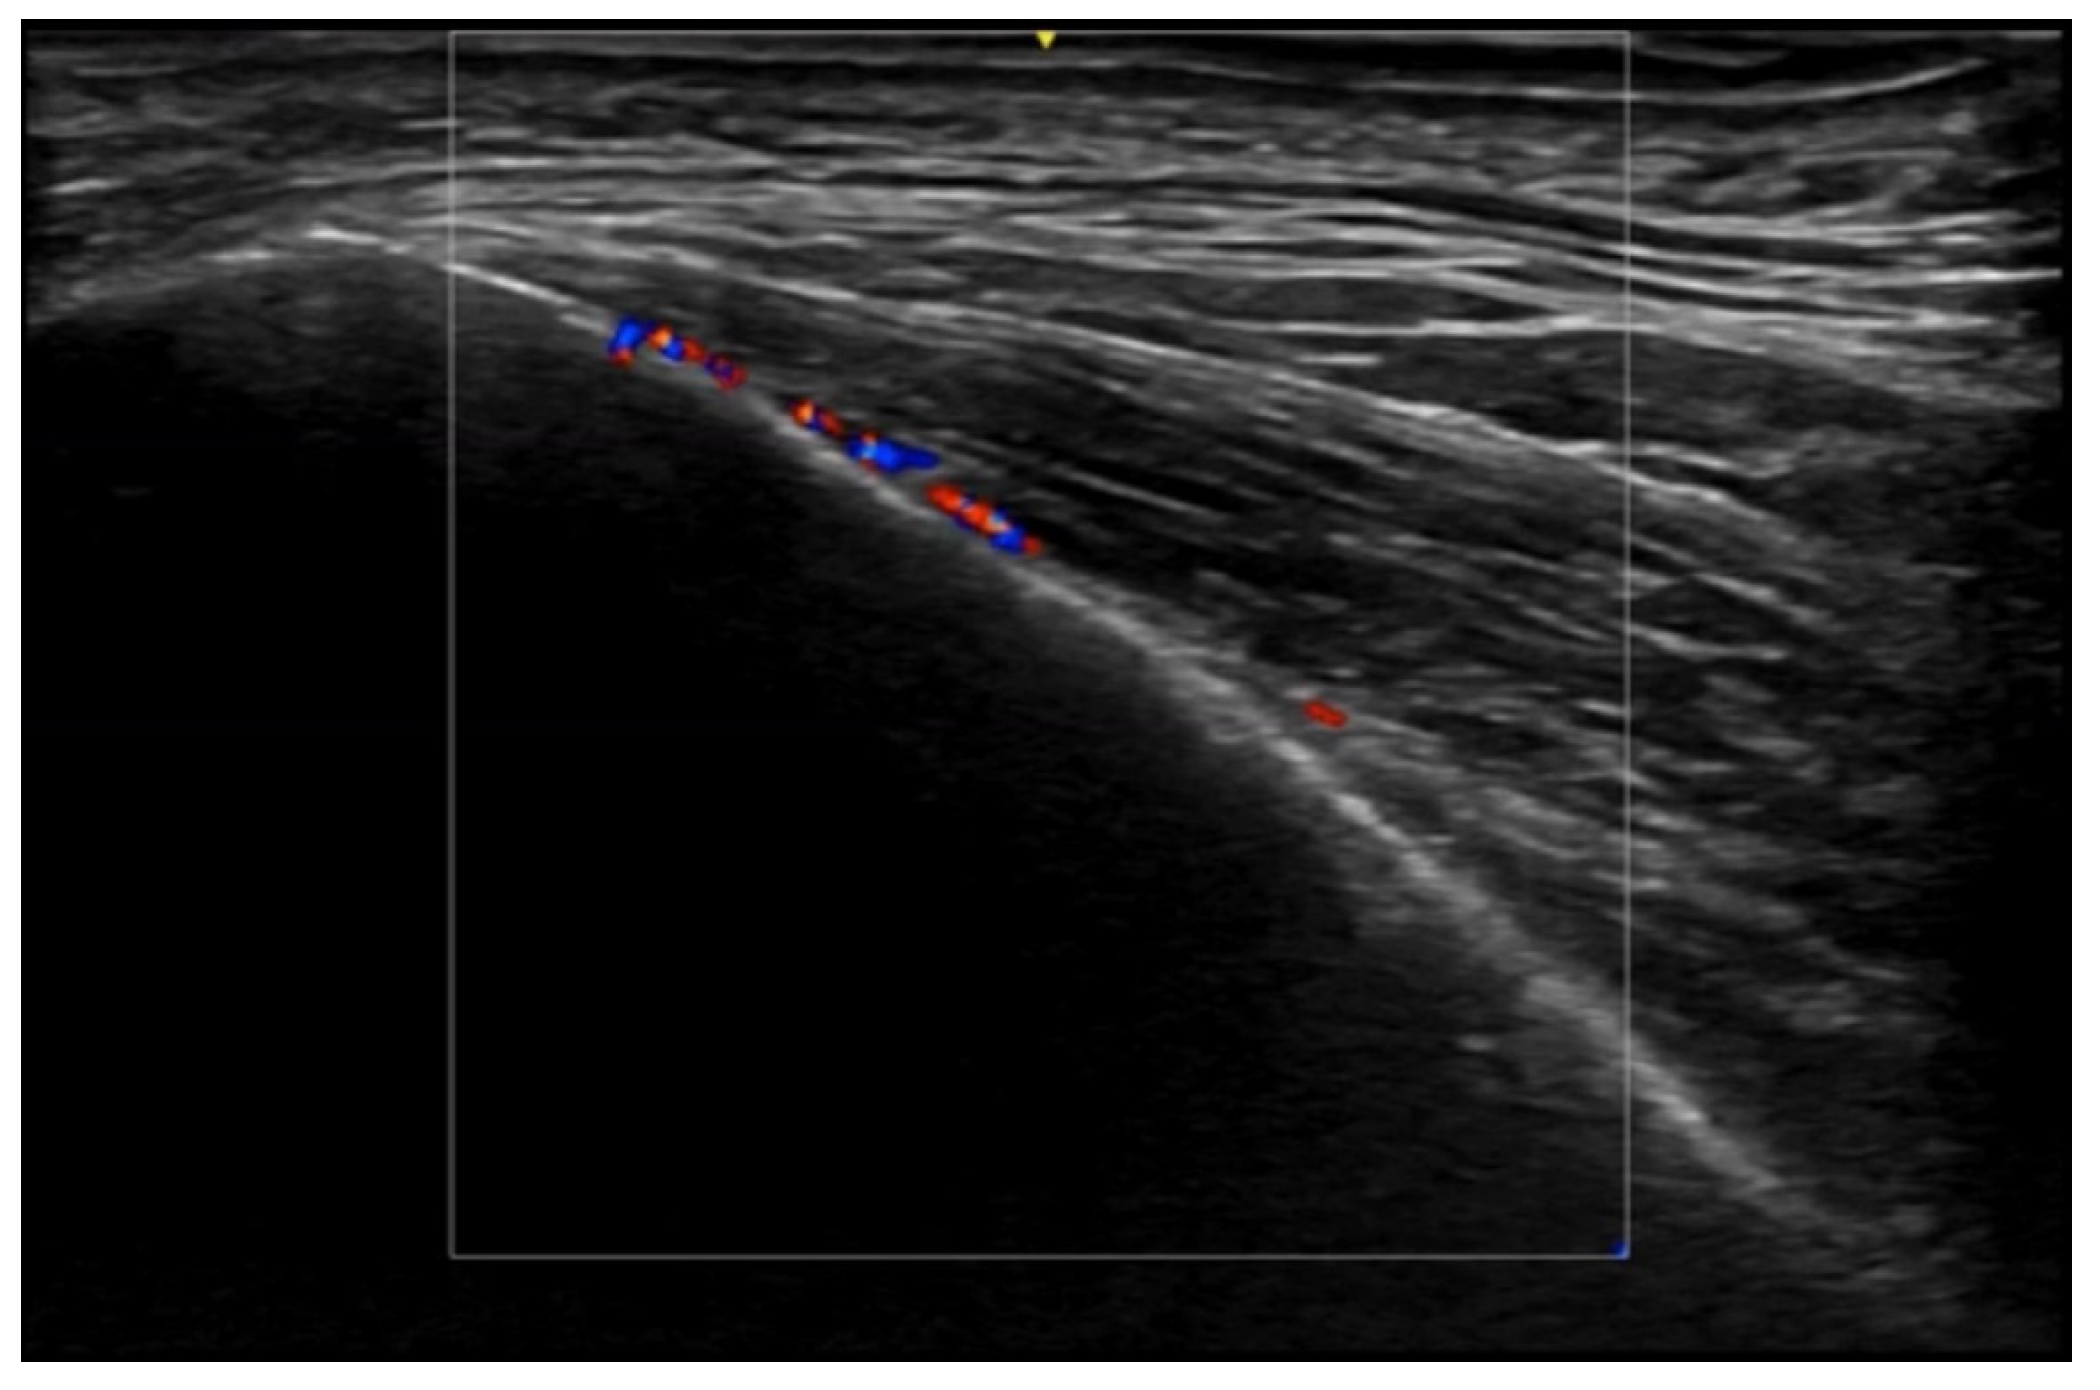

5. Specific Cutaneous Structure and Sites of Skin Disorders